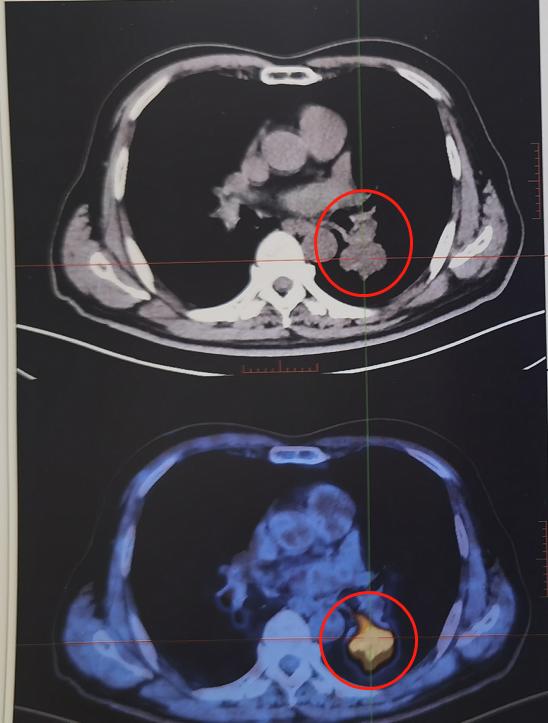

03. 于是进行了PET/CT代谢显像,进行肿瘤分期,依据结果,考虑为左下肺鳞癌Ⅱa期,T2bN0M0(AJCC,2018版,肺癌分期)

FDG-PET/CT显像,提示病灶呈明显葡萄糖代谢增高,SUV最大值为10.2。